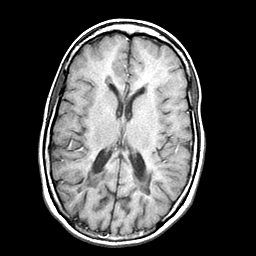

Multiple Sclerosis, MR Study mr-t1 -- Slice #12

[Home][Help][Clinical] Slice 12